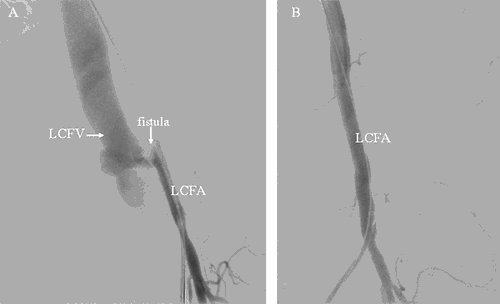

On post trauma day 31 the patient underwent repeat angiogram which revealed recurrence of bilateral common femoral AVFs. A left large pseudoaneurysm was present with proximal buckling of the stent-graft. This created a type 1a endoleak where flow traveled proximally around the stent-graft. On the right there was evidence of both a type 1a and type 1b endoleak, where flow traveled proximally and distally around the stent-graft causing the entire stent to be floating in a large pseudoaneurysm. On the left, 9 mm x 10 cm and 9 mm x 5 cm Viabahn stent-grafts were utilized to exclude the recurrent AVF and pseudoaneurysm in the common femoral artery (Figure 6).

Figure 6. A. Recurrent left sided AVF, prior to stent deployment. Fistula is seen between the common femoral artery and vein. B. Angiogram after stent deployment. Fistula no longer visualized. LCFV=left common femoral vein; LCFA=left common femoral artery.